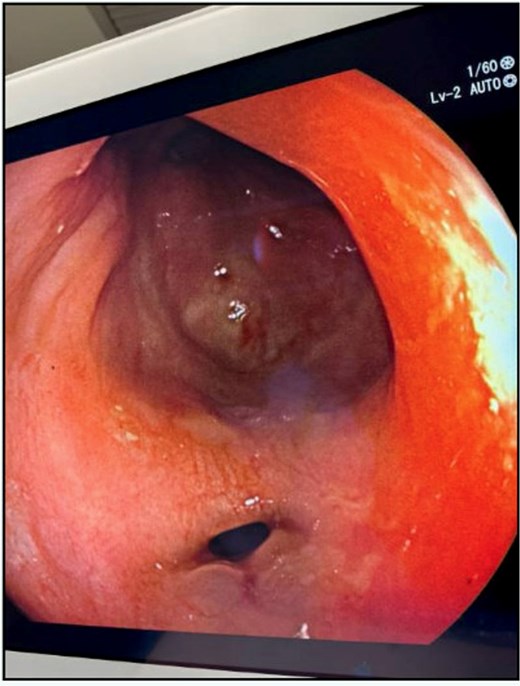

The patient’s leukocytosis resolved during hospitalization, and she was discharged on hospital day 5 with dietary modifications, including a low-fiber diet. At 4-week follow up, flexible sigmoidoscopy demonstrated near-complete healing of the rectal perforation, with only minimal residual mucosal disruption (Fig. 3). By 6 weeks post-injury, follow-up flexible sigmoidoscopy confirmed complete mucosal healing and restoration of normal rectal wall architecture, though mild rectal stenosis persisted (Fig. 4). The patient remained asymptomatic with resolution of her initial symptoms.

Follow-up flexible sigmoidoscopy at 4 weeks showing near-complete healing of the rectal perforation, with a small residual mucosal disruption.